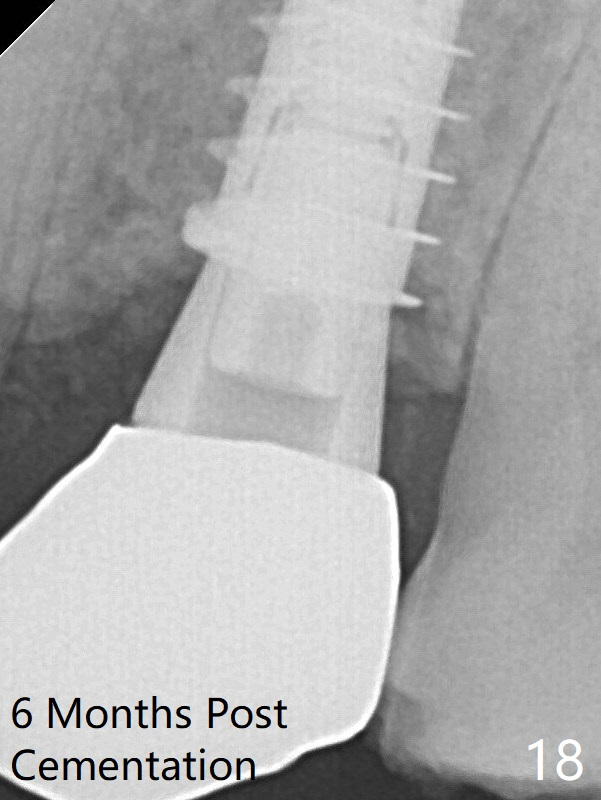

After allograft is placed around the implant, a 4.5x4(3) mm abutment is placed (Fig.10 A). Bitewing shows that the implant is not placed as deep as PA indicates. There is no bone loss 4 months postop (Fig.16). The crestal bone is denser 6 months post cementation (Fig.18).